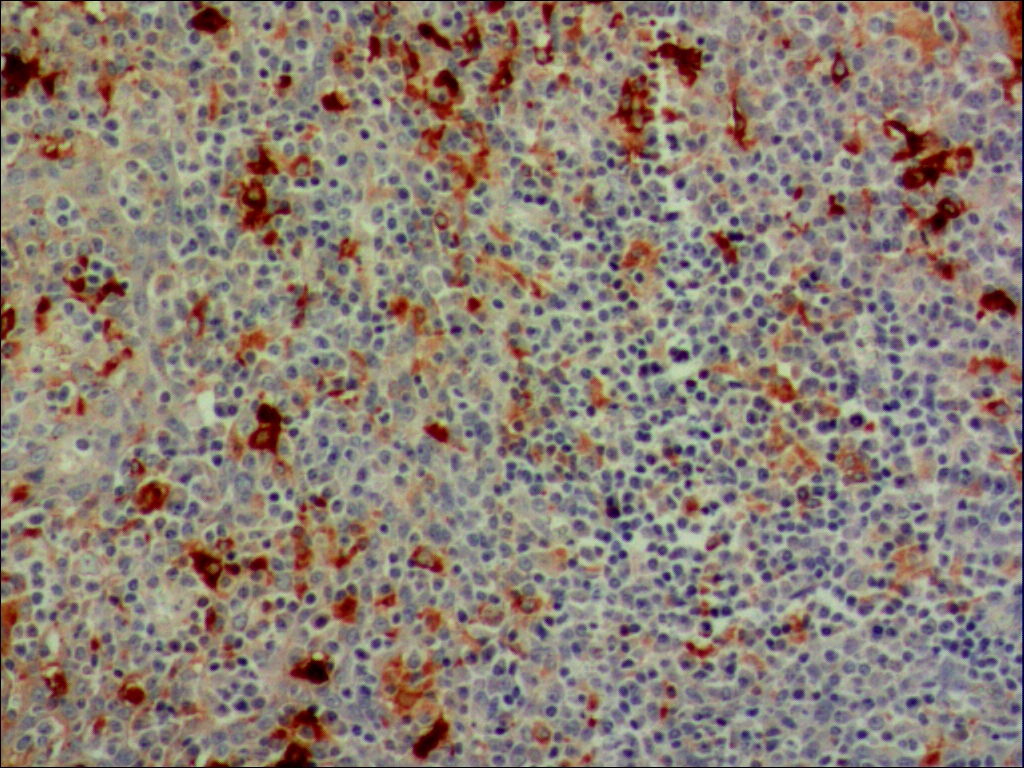

| 适用组织: | 冷冻切片/石蜡切片 |

| 阳性部位: | 细胞质 |

| 阳性对照: | 扁桃体 |

| 特异性 : | 此抗体与来自人血清的α-1-抗胰糜蛋白酶反应。 |

| 推荐效价: | •原液使用前应以适当比例稀释 推荐稀释度为1:100~1:200 •工作液不必稀释,直接滴加使用 |